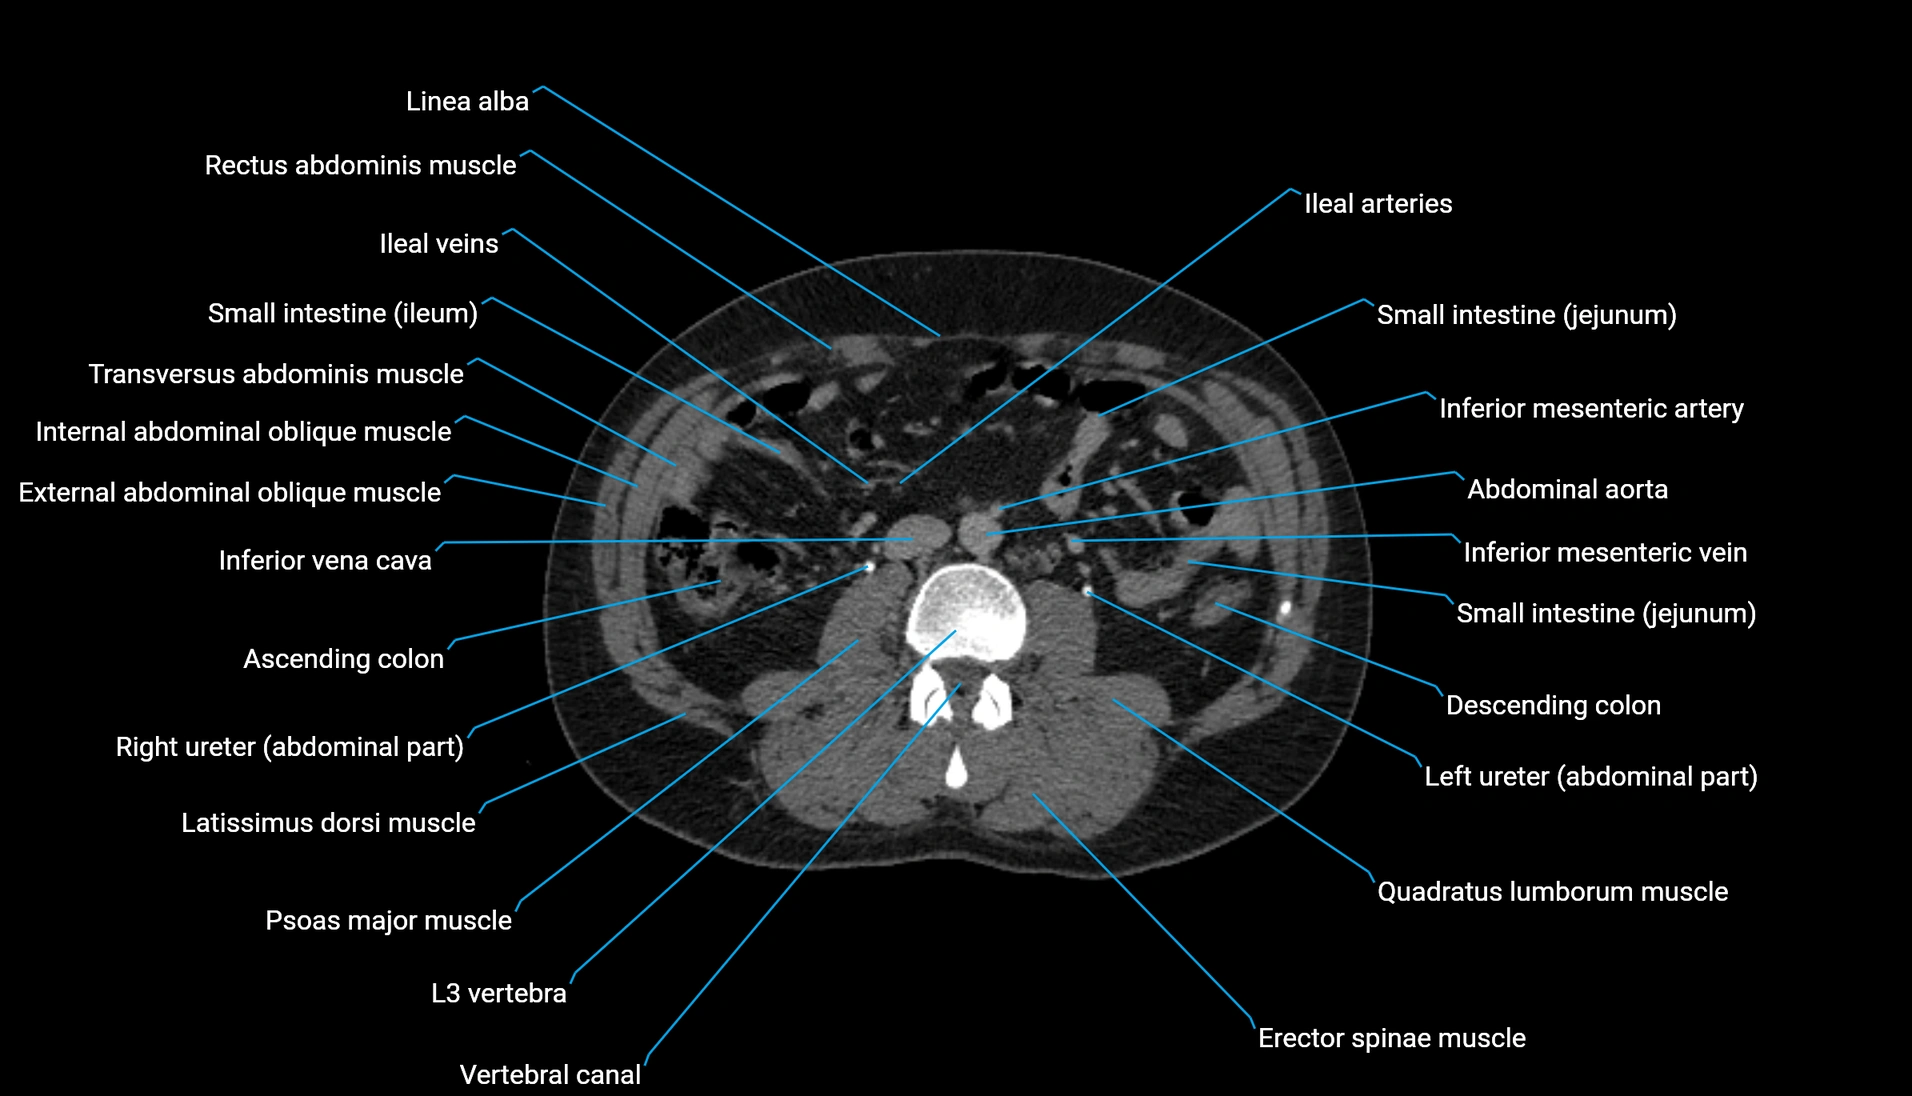

CT Appearance

Non-contrast CT:

-

Demonstrates cortical bone of acetabular rim in excellent detail

Detects fractures, dysplasia, retroversion, or bony overcoverage (pincer impingement)

3D reconstructions used in preoperative hip surgery planning

CT VRT 3D image

CT image